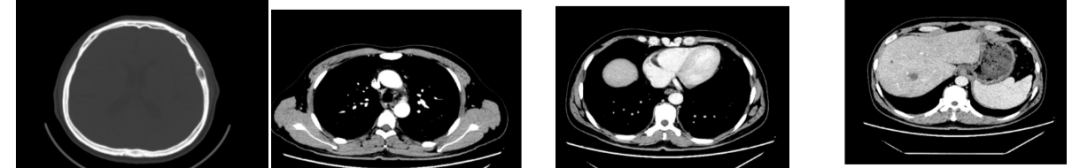

2018-11-14 CT(8周期化疗后):PD?

△基线水平

△治疗后

胃壁代谢稍增高但未见明确的肿物,肝内低代谢结节考虑转移瘤治疗后活性减低,纵膈及右肺门两个淋巴结代谢增高,考虑转移瘤活性尚存、左侧颞骨局部骨质破坏并代谢增高,考虑转移瘤。